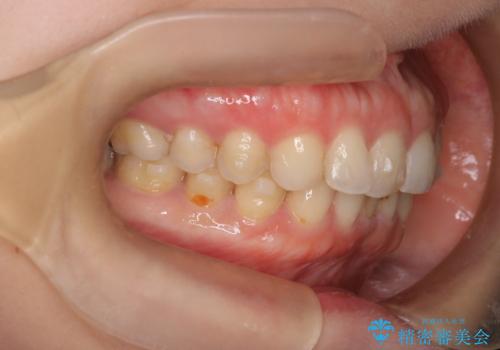

- 下顎前歯の叢生を主訴に来院されました。

臼歯関係の状態から下顎前歯一本の抜歯を行う治療計画を立て、インビザラインを使用して治療を行いました。

今回の抜歯ケースはインビザラインでも綺麗に治ります。